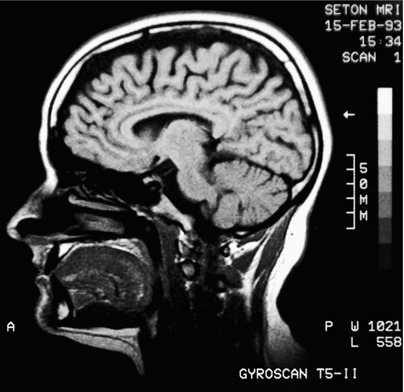

就像望远镜的发明一样,20世纪90年代中期和2000年代引入的MRI机器和各种先进的大脑扫描技术已经改变了神经科学。在过去的十五年里,我们对大脑的了解超过了此前所有人类历史,而曾经被认为无法触及的心智,终于成为了中心舞台。

无线电波,一种电磁辐射,可以穿透组织而不造成损害。MRI机器利用了这一事实,允许电磁波自由穿透头骨。在这个过程中,这项技术为我们提供了一些曾被认为不可能捕捉的东西的精美照片:大脑在体验感觉和情绪时的内部运作。观看MRI机器中闪烁的光舞,人们可以追踪在大脑内移动的思想。这就像能够看到时钟滴答作响时的内部一样。

你注意到MRI机器的第一件事是巨大的圆柱形磁线圈,它们可以产生比地球磁场强两万到六万倍的磁场。巨大的磁铁是MRI机器重达一吨、填满整个房间并花费数百万美元的主要原因之一。(MRI机器比X射线机器更安全,因为它们不产生有害离子。CT扫描虽然也能创建3D图片,但会用比普通X射线多许多倍的剂量冲击身体,因此必须小心调节。相比之下,MRI机器在正确使用时是安全的。然而,一个问题是工作人员的疏忽。磁场强大到足以在错误时间开启时将工具高速抛射通过空气。人们已因此受伤甚至死亡。)

MRI机器的工作原理如下:患者平躺着被推入包含两个大型线圈的圆筒中,这些线圈产生磁场。当磁场开启时,你体内原子的原子核就像指南针的指针一样:它们沿着磁场方向水平排列。然后产生一个小的射频能量脉冲,使我们体内的一些原子核翻转到相反方向。当原子核稍后恢复到正常位置时,它们会发出二次射频能量脉冲,然后由MRI机器进行分析。通过分析这些微小的”回声”,可以重建这些原子的位置和性质。就像蝙蝠使用回声来确定路径中物体的位置一样,MRI机器产生的回声使科学家能够重建大脑内部的清晰图像。计算机然后重建原子的位置,为我们提供美丽的三维图表。

当MRI最初引入时,它们能够显示大脑及其各个区域的静态结构。然而,在1990年代中期,发明了一种新型MRI,称为”功能性”MRI或fMRI,它检测大脑血液中氧气的存在。(对于不同类型的MRI机器,科学家有时在”MRI”前面加上小写字母,但我们将使用缩写MRI来表示所有各种类型的MRI机器。)MRI扫描无法直接检测神经元中的电流,但由于氧气是为神经元提供能量所必需的,含氧血液可以间接追踪神经元中电能的流动,并显示大脑各个区域如何相互作用。

这些MRI扫描已经明确推翻了思维集中在单一中心的观点。相反,可以看到电能在大脑思考时在不同部分之间循环。通过追踪我们思想的路径,MRI扫描为阿尔茨海默病、帕金森病、精神分裂症和许多其他精神疾病的性质提供了新的见解。

MRI机器的巨大优势在于它们精确定位大脑微小部分的精湛能力,精确到毫米的几分之一。MRI扫描不仅会在二维屏幕上创建称为像素的点,还会在三维空间中创建称为”体素”的点,产生数万个彩色点的明亮集合,呈现大脑的三维形状。